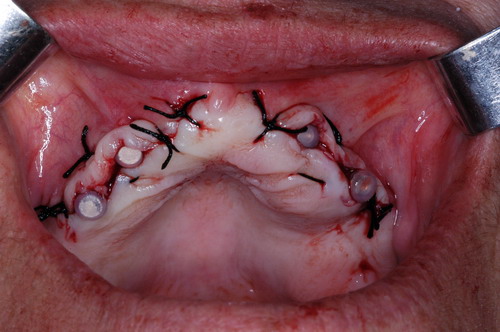

EL USO DEL ARCO GÓTICO DE GYSI , MEDIANTE UNA BÓVEDA PALATINA Y UN APOYO CENTRAL ÚNICO (BO PA YA CU) , EN LA UBICACIÓN DE LA RELACIÓN CÉNTRICA EN UN CASO DE GRAN LAXITUD TENDINOSA CAPSULAR. EL PACIENTE SE PRESENTA A CONSULTA CON UNA EDENTACIÓN PARCIAL, Y GRADO DE MOVILIDAD EXTREMO EN TODAS SUS PIEZAS REMANENTES. SE ESTUDIA EL CASO RADIOGRÁFICA Y CLÍNICAMENTE , Y EL PACIENTE RELATA ESTAR EN ESE ESTADO DESDE HACE MUCHO AÑOS. AL MANIPULAR LA MANDÍBULA EN UN INTENTO DE CONOCER EL ESTADO MUSCULAR DEL SISTEMA, SE OBSERVA UNA GRAN LABILIDAD TENDINOSA CAPSULAR QUE SE MANIFIESTA EN UNA HIPER LAXITUD EN LOS MOVIMIENTOS MANUALMENTE INDUCIDOS DE AMBOS CÓNDILOS DENTRO DE LA CAVIDAD. SE TOMAN IMPRESIONES Y SE MONTA EN UN ARTICULADOR SEMI AJUSTABLE , CORTANDO EN EL YESO LAS PIEZAS QUE SERÁN EXTIRPADAS , CONSERVANDO UNICAMENTE , AMBOS PRIMEROS PREMOLARES INFERIORES , QUE SERÁN UTILIZADOS PARA RETENER MEDIANTE RETENEDORES ELÁSTICOS LA PRÓTESIS INFERIOR , EN LA PRESUNCIÓN DE LA HIPERMOVILIDAD A QUE SERÁ SOMETIDA DADO QUE EN LA GRAN REABSORCIÓN ÓSEA , ES FRECUENTE EL ACERCAMIENTO DE TODAS LAS INSERCIONES MUSCULARES A LA PORCIÓN SUPERIOR DEL REBORDE ÓSEO , LO QUE ATENTARÁ CONTRA LA ESTABILIDAD DE DICHA PRÓTESIS PROVISIONAL. EN UNA PRIMERA SESIÓN CLÍNICO QUIRÚRGICA , SE EXODONCIA TODO EL SECTOR INCISIVO Y CANINO INFERIOR , Y AL OBSERVAR EL REMANENTE ÓSEO CANINO DE AMBOS LADOS , SE IMPLANTA EN FORMA INMEDIATA . TANSCURRIDOS DOS MESES , DONDE LA CICATRIZACIÓN ES ADECUADA , Y LA DINÁMICA MANDIBULAR ACEPTABLE , SE PROCEDE A LA ETAPA QUIRÚRGICA IMPLANTARIA MEDIANTE IMPLANTES SEMI SUMERGIDOS, CON ALGUNAS ZONAS DE REGENERCIÓN ÓSEA GUIADA FIG17 FIG18 FIG19 FIG26 DURANTE LA ETAPA DE CICATRIZACIÓN DE ESTE NUEVO ABORDAJE QUIRÚRGICO , SE ENDODONCIAN AMBOS PREMOLARES INFERIORES CONSERVADOS , LOS QUE EN UN FUTURO , CUANDO YA NO SIRVAN PARA RETENER LA PRÓTESIS REMOVIBLE PROVISORIA INFERIOR , SERÁN CORTADOS COMO RESERVA DE CAPITAL ÓSEO O BIEN COMO ELEMENTO RETENEDOR ANTE CUALQUIER TIPO DE INCIDENCIA IMPLANTARIA. ABORDAMOS LA ETAPA PRIMARIA PROTÉTICA , UNA VEZ TRANSCURRIDOS TRES MESES, MEDIANTE LA UTILIZACIÓN DE CUBETAS INDIVIDUALES , A LAS QUE REALIZAMOS UN RECORTE MUSCULAR EN BASE A STENS VERDE , COMO SI DE UNA PRÓTESIS COMPLETA SE TRATARA. DE ESE MONTAJE OBTENEMOS DOS RODETES DE METACRILATO , PERFECTAMENTE ADAPTADOS A LOS MODELOS FUNCIONALES , A LOS QUE LES OTORGAMOS LA PLANIMETRÍA DERIVADA DEL PARALELISMO CON EL PLANO DE FRANKFURT , Y UNA ALTURA (DV) QUE RESULTA DE LOS MÉTODOS MÉTRICOS DE DIMENSIÓN VERTICAL… Y QUE NOS SERVIRAN ADEMÁS DE TOMAR UNA NUEVA IMPRESIÓN FUNCIONAL MEDIANTE RECORTE MUSCULAR , PARA ADAPTAR UN DISPOSITIVO CONSISENTE EN UNA BÓVEDA PALATINA SUPERIOR , Y UN TORNILLO CENTRAL INFERIOR , LOS QUE DESPUÉS DE UN ENTRENAMIENTO ADECUADO DEL ENFERMO , NOS PERMITIRÁ REPRODUCIR EN EL BÓVEDA , EL ARCO GÓTICO DE GYSI , ENCONTRANDO DE ESTA MANERA LA OCLUSIÓN EN RELACIÓN CÉNTRICA. ACTUALMENTE ESTE MÉTODO HA SIDO RECREADO MEDIANTE LA DENOMINACIÓN DE: FIG50 FIG51 FIG52 OBTENIDO EL DIBUJO DEL ARCO GÓTICO , INSINUAMOS EN EL VÉRTICE DEL MISMO UNA PERFORACIÓN QUE FIJARÁ LA PUNTA DEL TORNILLO EN ESA POSICIÓN: RELACIÓN CÉNTICA FIG55 FIG56 FIG57 CON ESTOS PARÁMETROS SE CONSTRUYEN DOS SOBREDENTADURAS ABROCHADAS EN RÓTULAS SUPRA IMPLANTES , QUE LE OTORGAN FIJACIÓN SUFICIENTE , DANDO A LA OCLUSIÓN TODOS LOS ELEMENTOS DE UNA: OCLUSIÓN MUTUAMENTE COMPARTIDA, REFERENCIA II CON UN ESQUEMA OCLUSAL DE : FUNCIÓN DE GRUPO BILATERAL POSTERIOR DE ACCIÓN CANINA DESPUÉS DE LAS REVISIONES PERTINENTES A LA SEMANA , EL MES Y LOS SEIS MESES DE TERMINADA LA REHABILITACIÓN , SE CITA AL ENFERMO PARA UN NUEVO CONTROL AL AÑO Y MEDIO Y SE OBSERVA UNA PERFECTA SITUACIÓN TISULAR , CLINICA Y RADIOGRAFICAMENTE CONTROLADA , Y ADEMÁS LA PERMANENCIA DEL MISMO ESQUEMA OCLUSAL OTORGADO DESDE EL PRINCIPIO. SE CONTROLA RADIOGRAFICAMENTE Y SE DA EL ALTA DEFINITIVA RECOMENDANDO EL CONTROL DOS VECES AL AÑO. REFERENCIAS: I : II. : III: